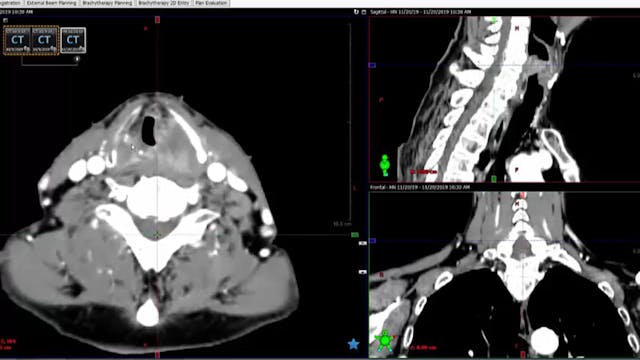

12/10/19 - Dr. Kenneth Hu - Radiation Oncology - Head and Neck US

Chartrounds US - Head and Neck Cancer